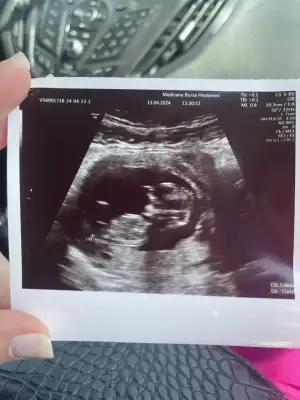

Kızlar merhaba bizimde ikili tarama vardı Ense kalınlığını söylemedi ama ince sıkıntı yok dedi burun kemiği oluşmuş Hersey yolunda dedi cinsiyet tahminim var dedi eşim söylemeyin dedi 🥲😒 22 nisanda söylicek 3 mayısda eşimin doğum gününde ögrencez pasta falan seçtim ama sizden tahmin istiyorum💙🩷😍

Kıza benzettim 😍

Nub paralel, kız bence💐